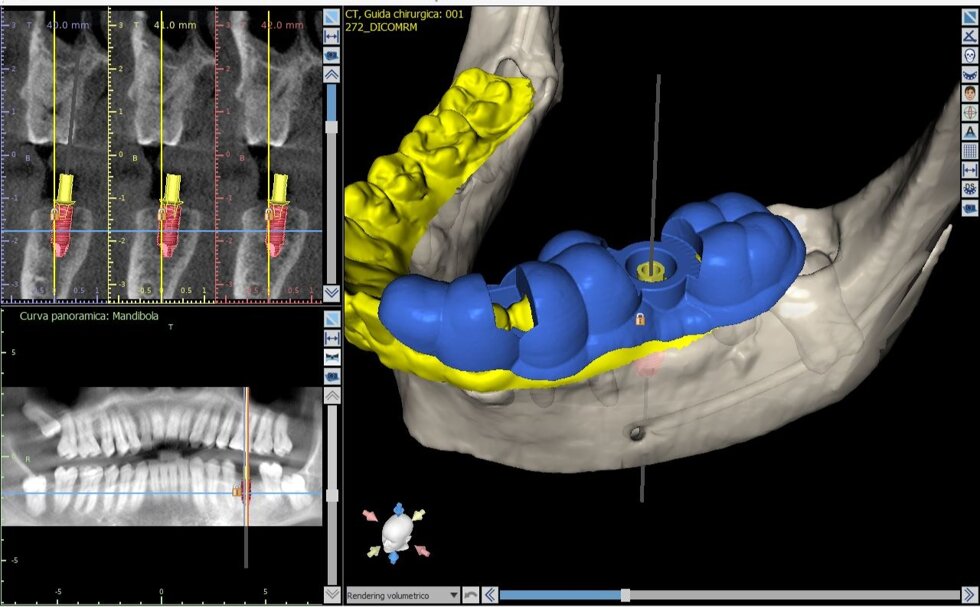

Il processo inizia con una tomografia computerizzata (CBCT), che fornisce un’immagine tridimensionale dettagliata delle arcate dentarie e delle strutture ossee. I dati vengono importati in software dedicati, dove il chirurgo può pianificare virtualmente l’intervento: scegliere la posizione, l’inclinazione e la profondità ottimali di ciascun impianto, valutando anche la densità ossea e la distanza da nervi o seni mascellari.

Una volta definito il piano chirurgico, si procede alla realizzazione di una dima chirurgica personalizzata, ottenuta tramite stampa 3D. Questa mascherina guida gli strumenti del chirurgo durante l’intervento, consentendo di inserire gli impianti nella posizione esatta prevista dal progetto digitale, senza necessità di ampie incisioni gengivali.

· altissima precisione nell’inserimento degli impianti;

· minore invasività e quindi riduzione di dolore, gonfiore e tempi di guarigione;

· interventi più rapidi e prevedibili;

· maggiore sicurezza grazie al controllo millimetrico delle strutture anatomiche;

· possibilità di carico immediato (applicazione della protesi nella stessa seduta) in casi selezionati.